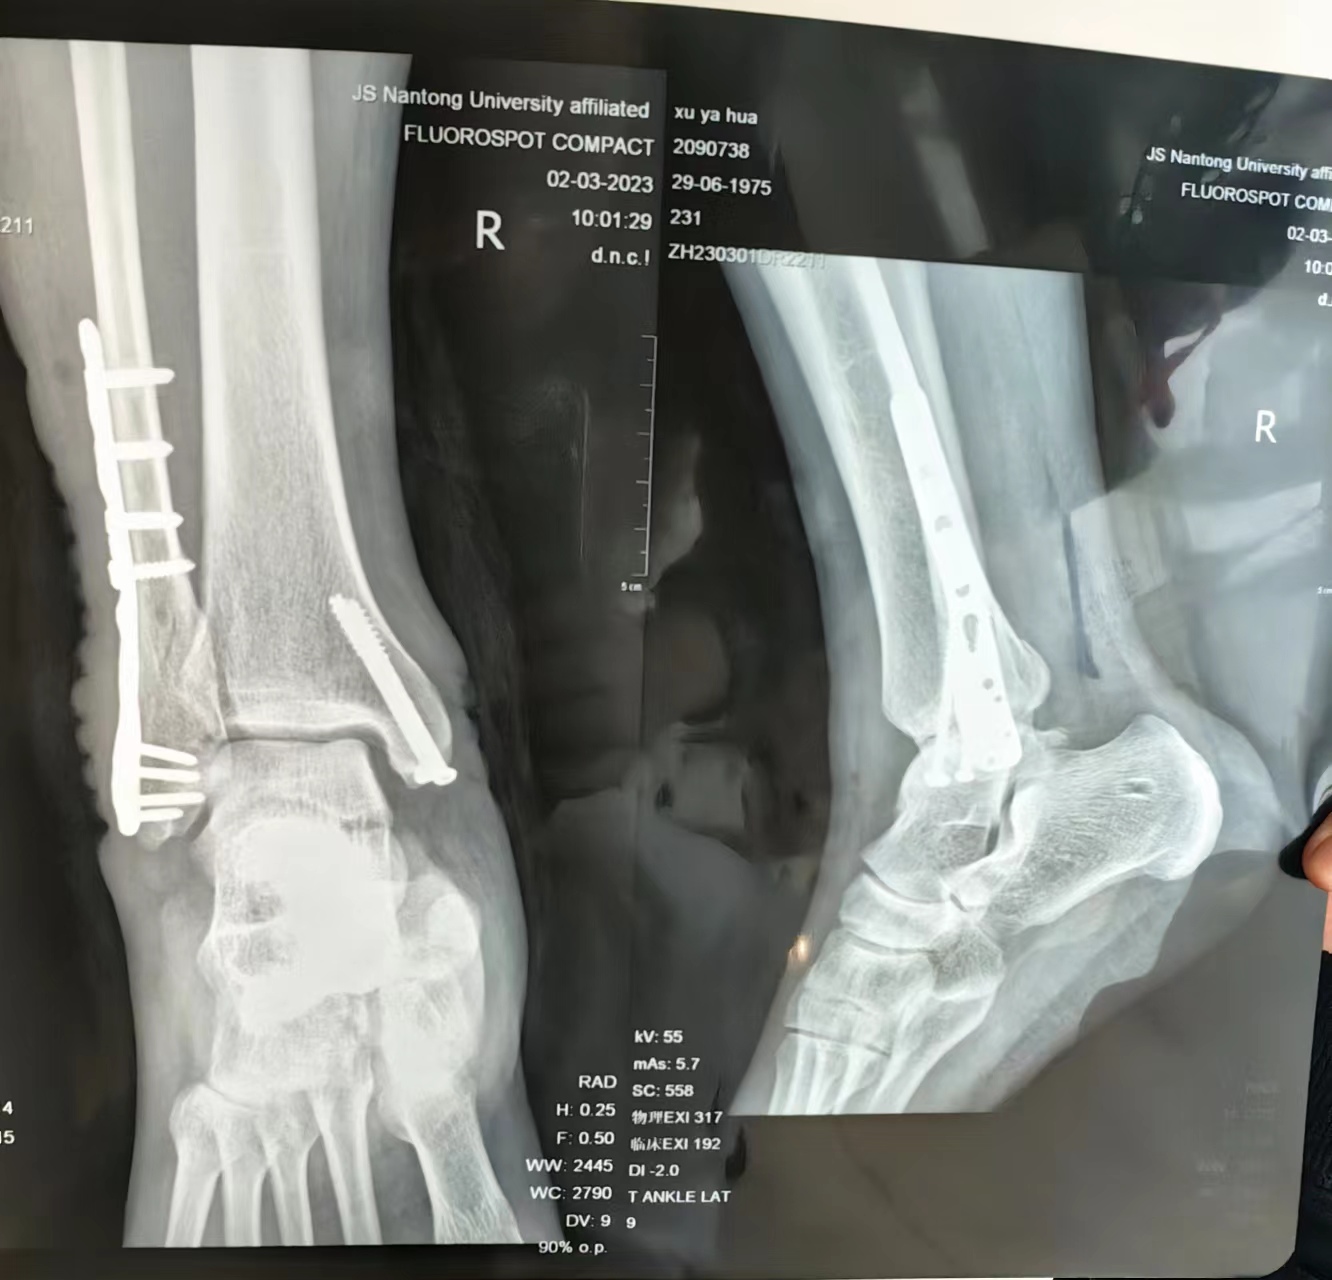

3月2日,DX片显示:右侧三踝骨折内固定术手,金属内固定在位,未见明显松动。骨折线模糊,断端对位对线可。

3月2日,术后DX片说,手术效果蛮好。